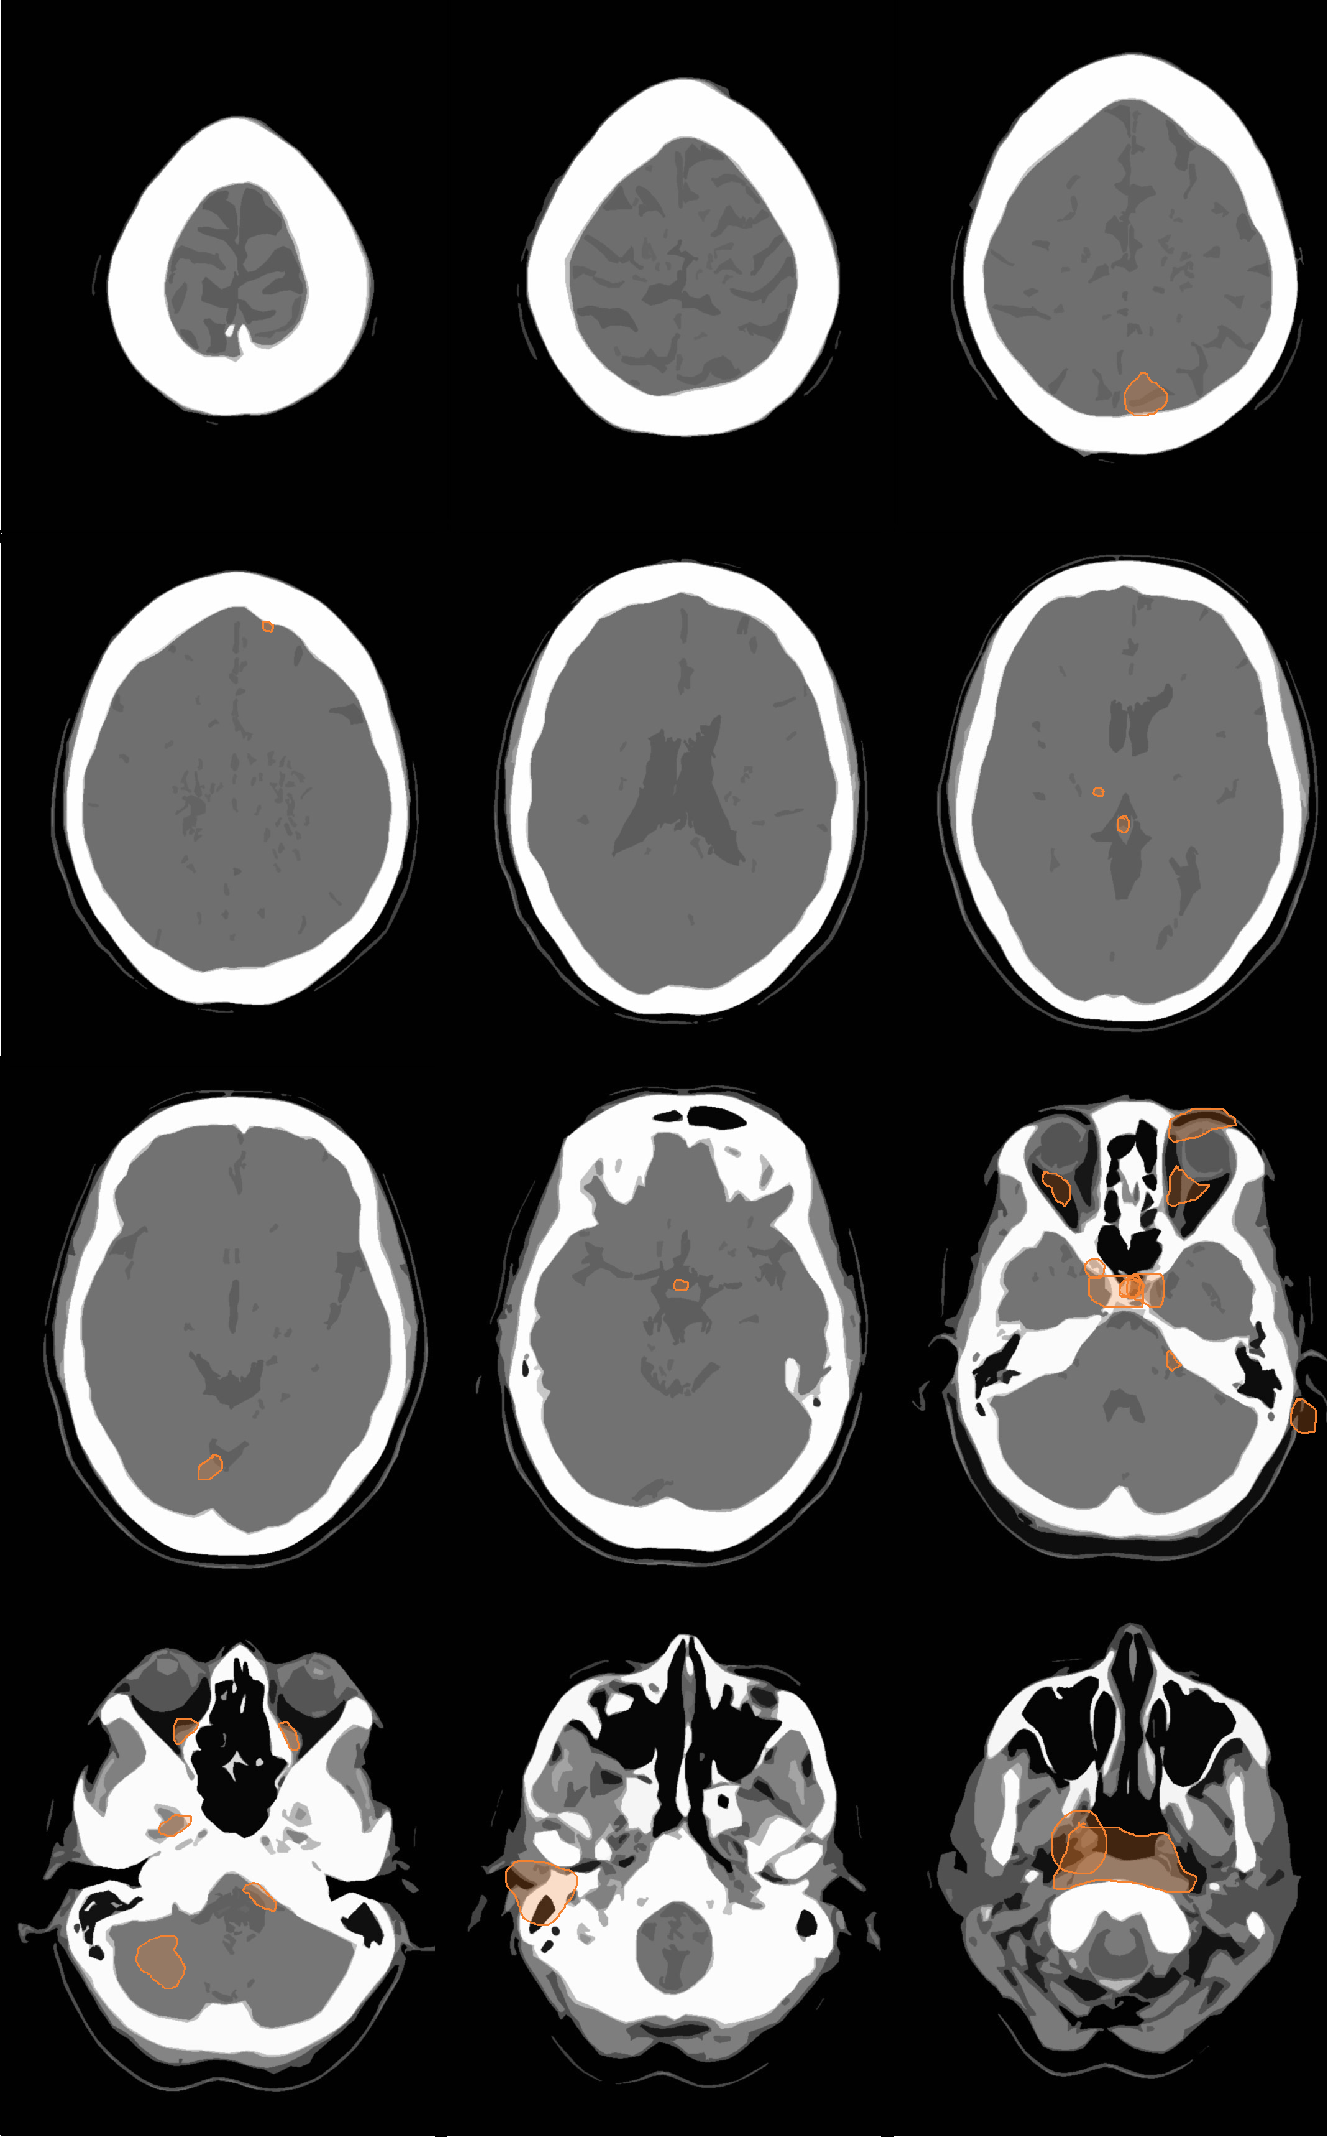

From jeffrad.org

MissMapCT HeadTrauma Head Trauma Exam Traumatic brain injury (tbi) is an acquired disruption of the normal function or structure of the brain caused by a head impact. Common acute head trauma exam questions for medical finals, osces and mrcp paces. A concussion is a mild traumatic brain injury that results from a bump, violent jolt or blow to your head. Examine the head for lacerations,.. Head Trauma Exam.